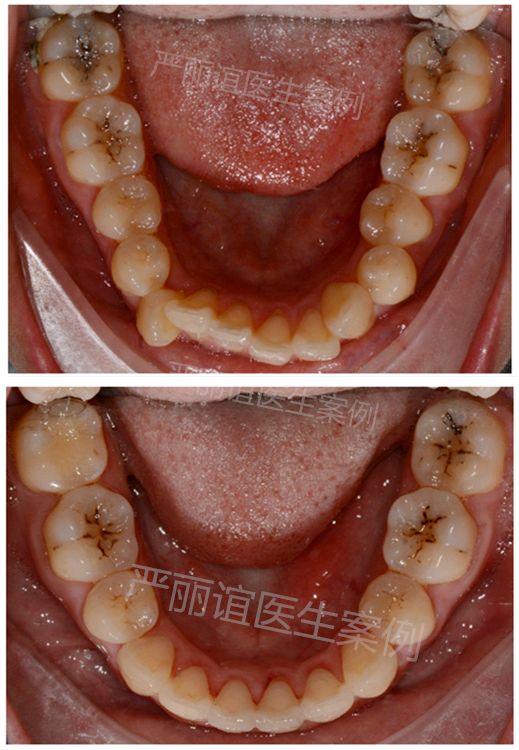

患者:成年女性

主诉:微笑时侧面牙齿前突影响美观,要求矫正。

结果:牙性前突(侧貌微突,笑起来牙齿倾斜外突)

矫正方案:拔牙矫正,拔除14 24 34 44,排齐整平上下颌牙齿,内收上下颌前牙,改善前牙倾斜度,改善侧貌。

矫正时间:1.5年。